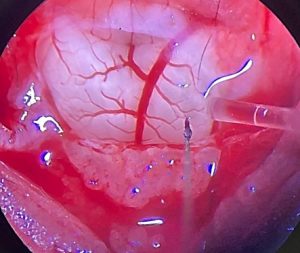

Using advanced neurophysiological approaches, including high-density neuronal recordings, optogenetics, and integrative in vivo physiological measurements, we investigate how brainstem circuits encode and integrate multimodal sensory information to regulate breathing, airway tone, and cardiovascular function. Rather than focusing on single neurons in isolation, our work emphasizes network-level organization, revealing how distributed neural populations dynamically coordinate homeostatic control.